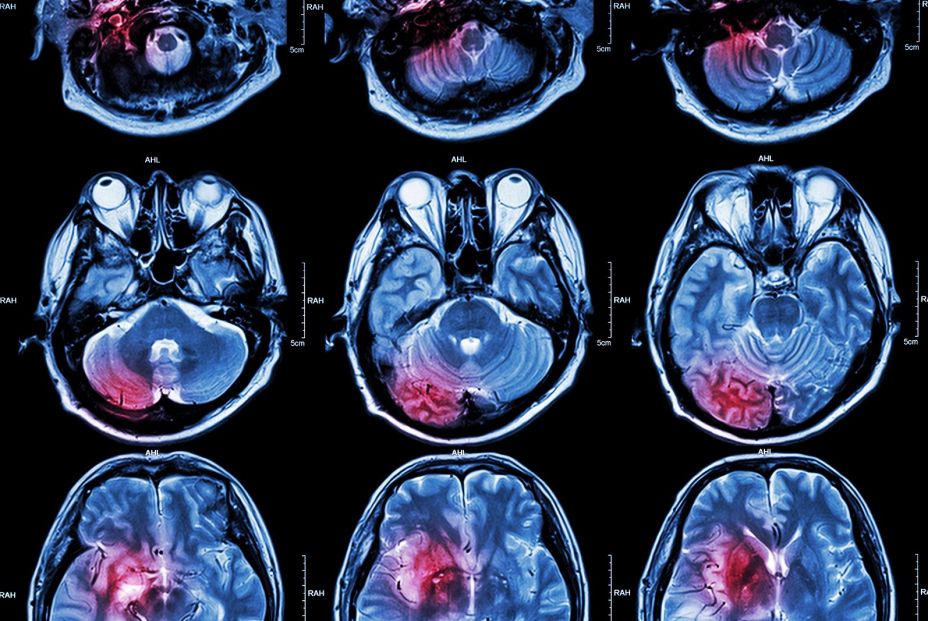

En radioterapia, cada milímetro cuenta: marcar correctamente los límites puede ser la diferencia entre preservar un órgano sano o comprometer la eficacia del tratamiento. OAR- Train proporciona un entorno seguro para que el personal sanitario en formación practique la delimitación de tumores y órganos de riesgo (OAR) en pacientes oncológicos. La plataforma ofrece casos reales, retroalimentación experta y un sistema de comparación con resultados de especialistas, lo que permite aprendizaje autónomo, práctica flexible y mejora continua.

La presentación del proyecto corrió a cargo de la Dra. Carolina de la Pinta, médica especialista en Oncología Radioterápica del HURyC e investigadora del IRYCIS, quien subrayó que “aunque la radioterapia es la herramienta más importante tras la cirugía en el tratamiento del cáncer, hasta ahora no existía un entorno digital seguro para entrenar el contorneo de órganos sin límite y sin riesgo para el paciente”.